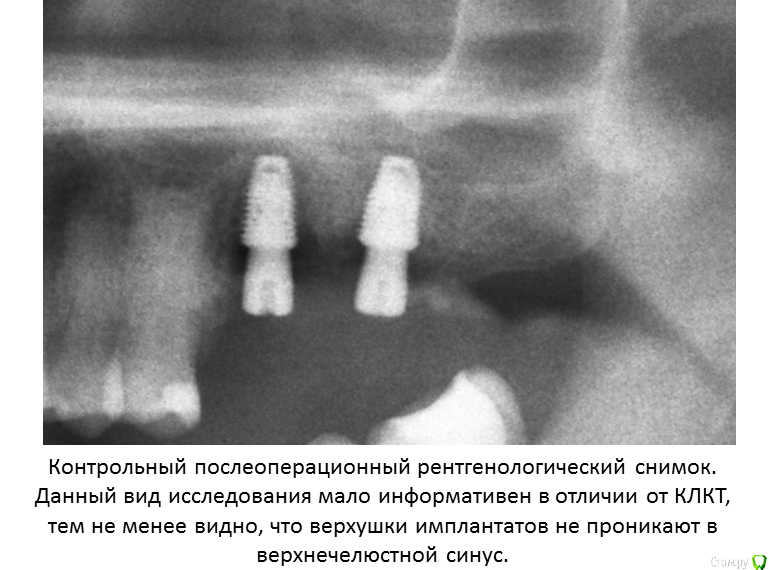

А я люблю при одномоментной имплантации цепануть верхушкой имплантата дно синуса для первичной стабильности и лунку закрыть сдт от внешнего воздействия.

Да, бикортикально, как вариант если необходима первичная стабильность